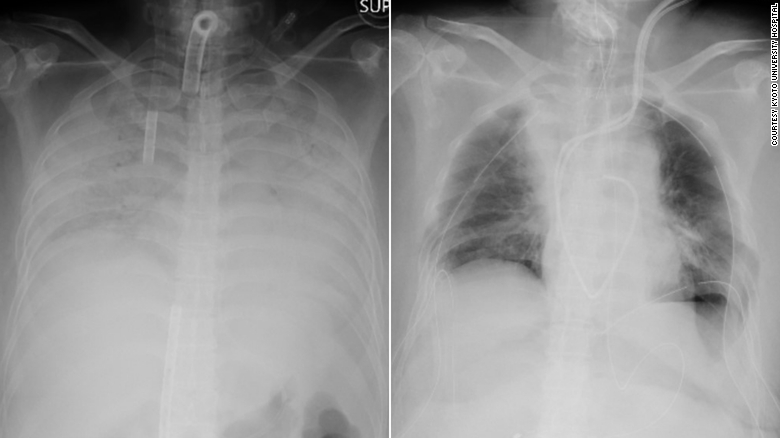

Японські медики повернули пацієнтці можливість дихати, провівши унікальну операцію з пересадки легенів. Цей випадок унікальний тим, що здавався безнадійним: жінка не могла самостійно дихати після перенесеного у важкій формі коронавіруса.

У середу, 7 квітня, група з 30 медичних фахівців Японії провела складну операцію з пересадки легеневої тканини. Операція тривала 11 годин. Донорами виступили чоловік і син пацієнтки. Операція проходила в медичному закладі, який розташований в Кіотському університеті. За словами фахівців, це перший і єдиний випадок трансплантації легеневої тканини від живих донорів.

Жінка із західної частини Японії заразилася коронавірусною інфекцією COVID-19 в кінці 2020 року. Кілька місяців пацієнтка перебувала на апараті, який не давав їй померти. За словами фахівців, хвороба настільки сильно пошкодила легені пацієнтки, що вони не могли нормально функціонувати.

Випадок пацієнтки вважали безнадійним, лікарі думали, що тут не можна нічим допомогти. Однак кілька наукових експертів запропонували свою допомогу, в результаті спільними зусиллями вчених і медиків вдалося досягти унікальних результатів.

Раніше подібну операцію пацієнтам з коронавірусом проводили в США. У цих пацієнтів була вражена значна частина дихальних органів. Однак японські фахівці пішли ще далі, і взяли матеріал у живих донорів. Родичі жінки самі запропонували свої послуги. Зараз чоловік і син пацієнтки в стабільному стані, а сама жінка все ще лежить в реанімації. Якщо відновлення пройде за планом, жінка може бути виписана з медичного закладу вже в червні.